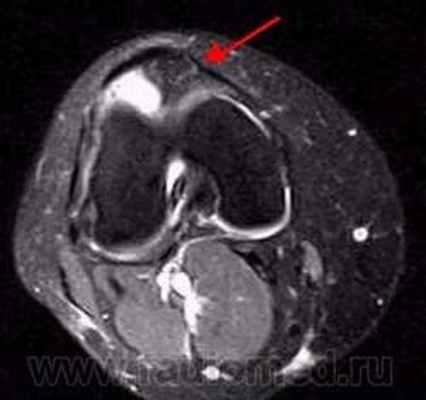

Пигментный виллёзонодулярный синовит - редкое заболевание с доброкачественным течением, характеризующееся пролиферативными изменениями синовиальной оболочки, отложением гемосидерина, образованием ворсинок, паннуса. Две разновидности: виллёзонодулярный бурсит и виллёзонодулярный тендосиновит. Частота - 2 на I 000 000. Преобладающий возраст • Виллёзонодулярный бурсит - 30-40 лет • Виллёзонодулярный тендосиновит -50-60 лет. Преобладающий пол - женский. Этиология. В 30% случаев развитию синовита предшествует травма сустава. Патоморфология. Пролиферация клеток синовиальных оболочек с образованием узлов, содержащих клеточный инфильтрат из фибробластов, лимфоцитов, макрофагов с жировыми включениями. Клиническая картина • Виллёзонодулярный бурсит -моноартрит. Чаще всего (80% случаев) поражается коленный сустав, реже - (с убывающей частотой) тазобедренный, голеностопный и плечевой суставы • Виллёзонодулярный тендосиновит - образование узелков в мышечных сухожилиях и связках сустава. Лабораторные исследования • Увеличение СОЭ • Синовиальная жидкость ксантохромная, с примесью крови • Биопсия синовиальной оболочки: узловая пролиферация, гемосидероз, инфильтрация мононуклеарными клетками. Рентгенологическое исследование • Остеопороз и наличие остеофитов нехарактерны • Артропневмография: множественные округлые дефекты наполнения синовиальной полости, обусловленные наличием узлов или гипертрофированных ворсинок синовиальной оболочки • МРТ - выявление гемосидерина и жировых включений. Артроскопия • Суставной хрящ приобретает коричневую окраску вследствие гемосидероза • Различной величины узлы коричневого цвета. Дифференциальный диагноз • Виллёзонодулярный бурсит • Липома - в аспиратах отсутствует ксантохромная жидкость • Остеоартроз - кисты возникают только на суставных поверхностях, подвергающихся нагрузке, тогда как при пигментном виллёзонодулярном синовите они образуются на всех суставных поверхностях. Остеофи-ты, напротив, более типичны для остеоартроза • Воспалительные арт-ропатии, дебютирующие моноартритом, - ревматоидный артрит, туберкулёзный артрит, анкилозирующий спондилоартрит и др. • Виллёзонодулярный тендосиновит - панглии (околосухожильные кисты): аспираты ганглиев содержат гелеподобную жидкость. Лечение хирургическое • Виллёзонодулярный бурсит • Тотальное иссечение синовиальной оболочки, вероятность рецидива заболевания составляет 25-40% • Лучевая терапия • Виллёзонодулярный тендосиновит - иссечение кист. Синоним. Синовит геморрагический МКБ. М12.2 Ворсинчато-узелковый (виллонодулярный) синовит (пигментный)

Результаты и их обсуждение артроскопии позволила дифференцировать характер поражения суставов у больных со сходной клинической картиной заболевания [9, 10], возможность изучить рельеф синовиальной оболочки на всем ее протяжении. В зависимости от давности синовита и особенностей его развития в данном суставе изменения синовиальной оболочки варьировали в очень широких пределах. Развитие воспалительного процесса в большинстве наблюдений сопровождалось ее утолщением, появлением гиперемии, пролиферации ворсин, образованием на ее поверхности фибриновых сгустков. Следует отметить, что одним из наиболее значимых параметров развития СХС может быть степень увеличения объема поражения синовиальной оболочки (СО), показателем который является выраженность ворсинчатой пролиферации [11]. Недостаточная эффективность внутрисуставных инъекций НПВП во многих случаях определялась относительной стойкостью к действию глюкокортикостероидов в результате значительного количества провоспалительных цитокинов в очаге воспаления [12]. В последующем нежная синовиальная оболочка трансформируется в довольно мощный тканевой массив (рис. 1).

Рис. 1. Выраженная ворсинчатая пролиферация, синовиальная оболочка превратилась в мощный тканевой массив. В суставе формируются пролиферативные изменения и сгустки фибрина. Произведено расширенная синовкапсулэктомия коленного сустава.

Рис. 5. А. Артроскопическая картина коленного сустава, при пигментно-ворсинчатом узелковом синовите (ПВУС). Б. После артротомии сустава.

В. Состояние хрящевого покрова. Хрящевой покров бедра и надколенника пропитан гемосидерином.